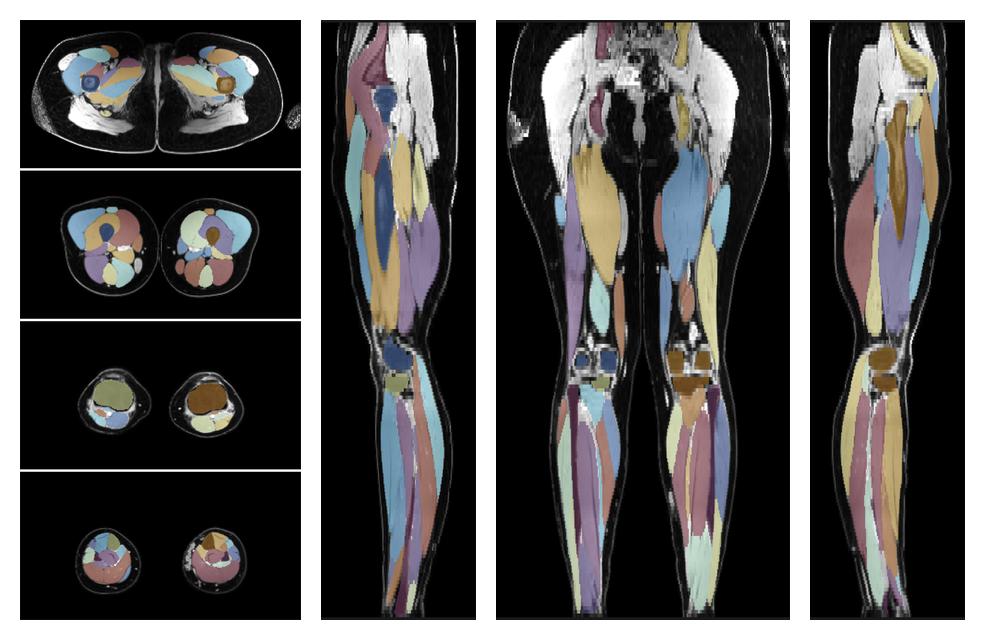

Muscle segmentation

Convolution neural network based (UNET) fiber automated muscle segmentation, for information look here».

• 3D volume render of automated muscle segmentation.

3D render of automated muscle segmentation labels generated using a CNN UNET.

• Automated muscle and bone segmentation.

Overlay of automated muscle segmentation labels on dixon water image.